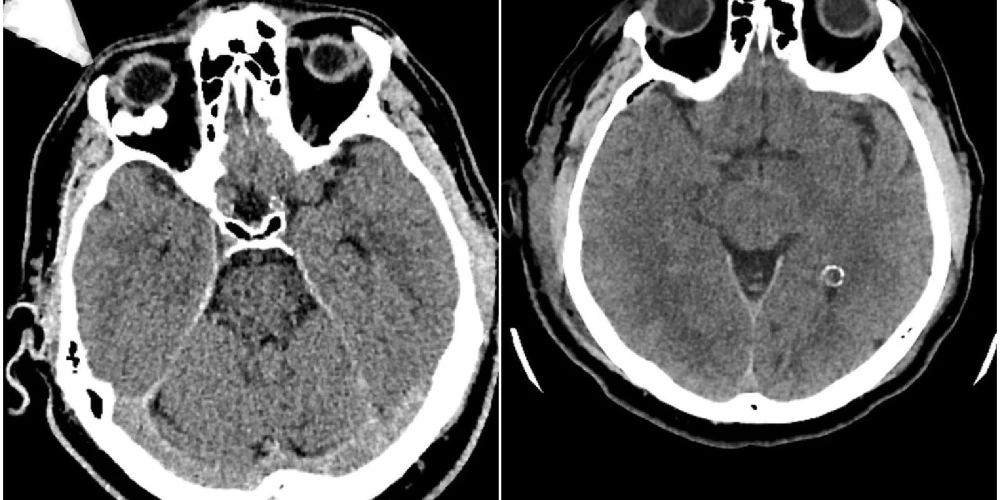

Par veselību16.01.2026Stradiņa slimnīcā veikta unikāla neiroķirurģiska operācija – caur galvaskausu izoperēts audzējs acs dobumā aiz acs ābola